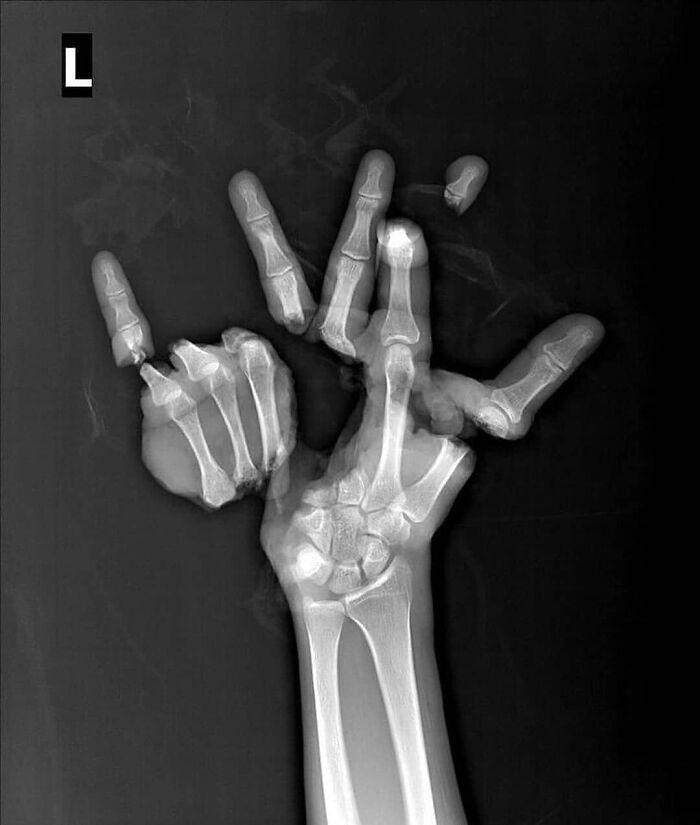

#37 Trauma Caused By An Agricultural Machine, Severing The Hand In Multiple Locations

Image credits: medicalpedia